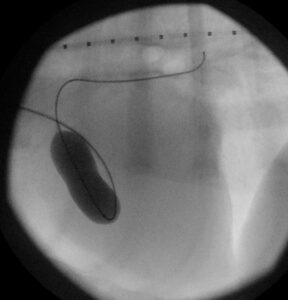

“We performed a pulmonary balloon valvuloplasty, which is keyhole heart surgery to insert a catheter into the blocked valve to stretch it open.

“This type of surgery is extremely tricky due to the technical challenge of moving catheters inside a very thickened, small heart.

“Despite these challenges and difficulties, the procedure was a success and the valve opened up well.”